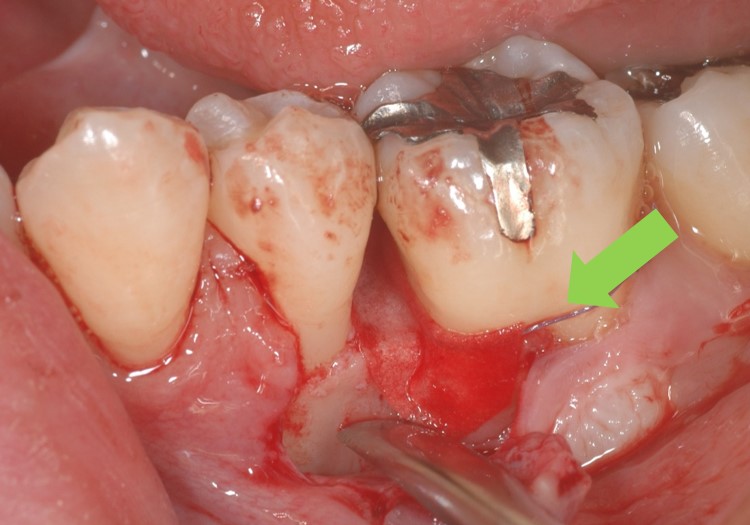

実際に歯肉を剥離したのが下写真です。オレンジ部分に骨吸収(歯周病で骨が喪失した部分)が確認できます。

下写真は骨欠損部分にGTR膜(遮断膜)を設置したところです。骨欠損部分が遮断膜で覆われ、歯肉が入り込むのを防ぎます。膜は白色ですが、血液を含んで赤く染まっています。